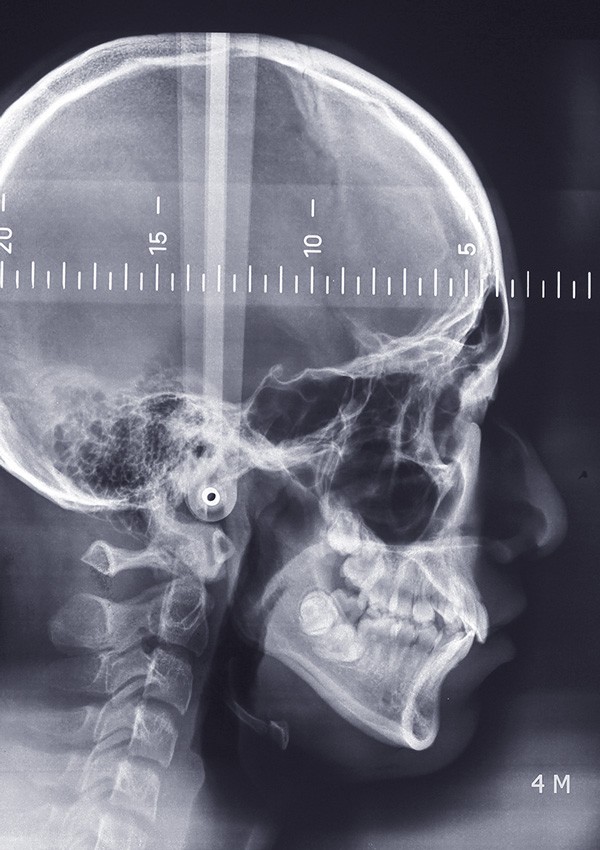

Sur le plan squelettique, le patient présente une classe I de Ballard sur un schéma hyperdivergent et une rotation postérieure de Björk. Le patient se situe au stade Cvs 4 de maturation des vertèbres cervicales, soit en plein dans son pic de croissance (fig. 10).